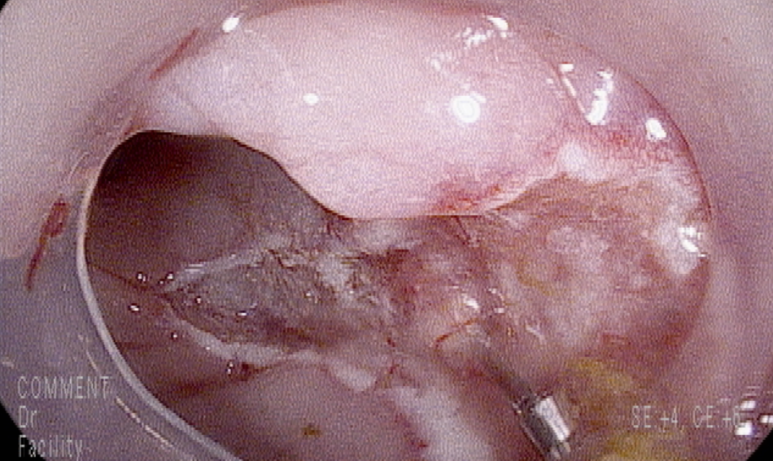

조직결과; sm3깊이까지 침범한 점막하 대장암 [ DIAGNOSIS ]Rectum, 9cm from anal verge, colonoscopic polypectomy; Submucosal adenocarcinoma with background of tubular adenoma a) level of invasion (for sessile lesion);deep third of submucosa (sm3 by Kikuchi classification) b) resection margin: possibly involved(+) 추가계획; 수술

내시경 치료의 절대적 기준치는 1000um이하로 보고 있으며...(점막하층 침윤이 1000um미만이면서 맥관이나 림프관의 침윤이 없는 경우는 LN meta전이가 0-5%정도로 보고됩니다.)

점막하층까지 침윤한 침습암의 경우 LN meta가 3-16% 동반될수 있습니다. --> 추가적 외과적 수술 필요